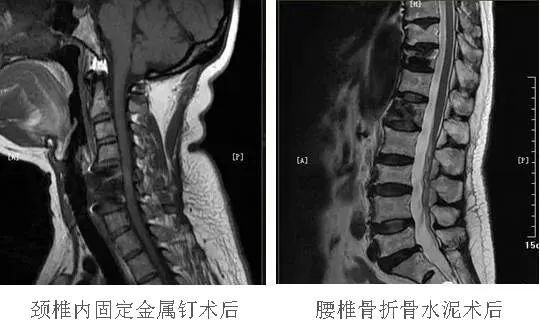

??2.骨科植入物

??由材质属性决定能不能做。骨科植入物常为钴铬钼合金、不锈钢、钛合金等材料,近年来使用的几乎都为弱磁性或非磁性,是可以做MRI。检查前应先咨询确定材质,再行MRI检查。

??3.外固定植入

??金属材料确定为钛及钛合金材质,可带入磁共振检查。故行MRI检查前,请务必先确认其材料及安全性,再行MRI检查。